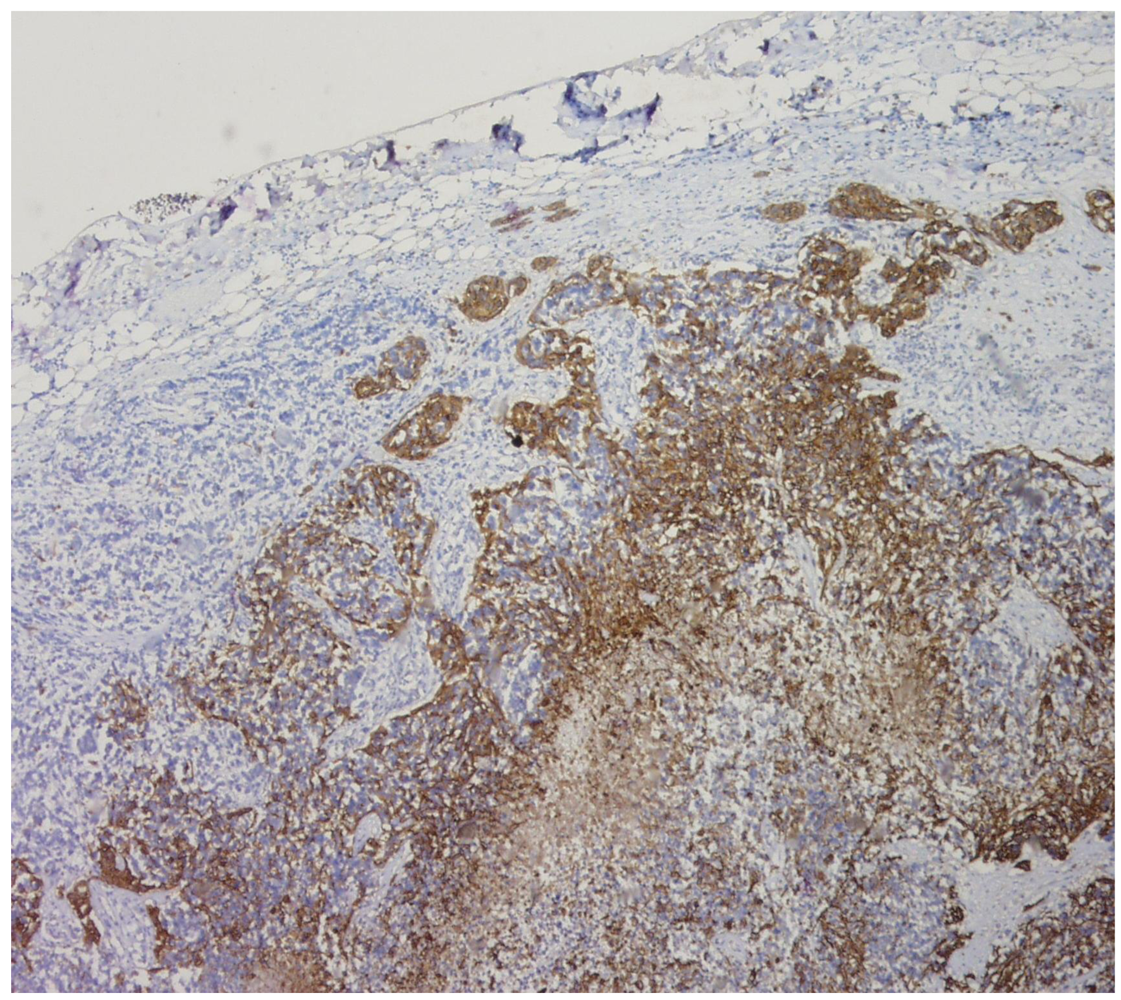

Unfortunately, the pancytopenia dramatically worsened and frequent red cell and platelet transfusions only had a slight effect. A macrophage-activation syndrome and adverse drug reaction were suspected. A lumbar puncture, a myelogram, and a unilateral iliac bone marrow aspirate and biopsy were suspected, in the aim to explicit this unusual pancytopenia and an ENM was diagnosed based on the presence of marked GFAP immunoreactive staining tumor cells. A course of chemotherapy, nitrosourea (fotemustine) was administered, but the patient's status rapidly deteriorated. He experienced back pain involving the cervical and lumbar regions and morphine was required. He continued to receive frequent red cell and platelet transfusions but finally died from a pyrexia pancytopenia syndrome.

The autopsy findings ruled out the possibility of a second primary tumor site. Post-mortem examination of the CNS did not reveal any other apart from lesions the initial tumor of the temporo-occipital lobe. The whole-body autopsy also reported diffuse metastasis in the lung, the mediastinal lymph nodes and in the spleen (Figure 2). No other primary tumor was detected.